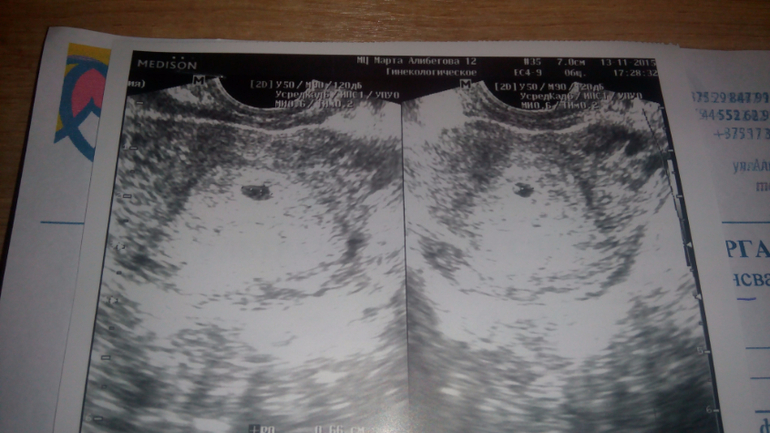

В пятницу была на узи. Плодное яйцо в матке и соответствует сроку по месячным! Ура!!! Уже 0,5 см)) Самое красивое ПЯ, которое я видела))))

Правда на узи увидели тонус. Добавила себе еще магния. Не хочу увеличивать дюфастон без назначения врача, а магний точно лишним не будет. Ну и днем ношпа, а на ночь папаверин.